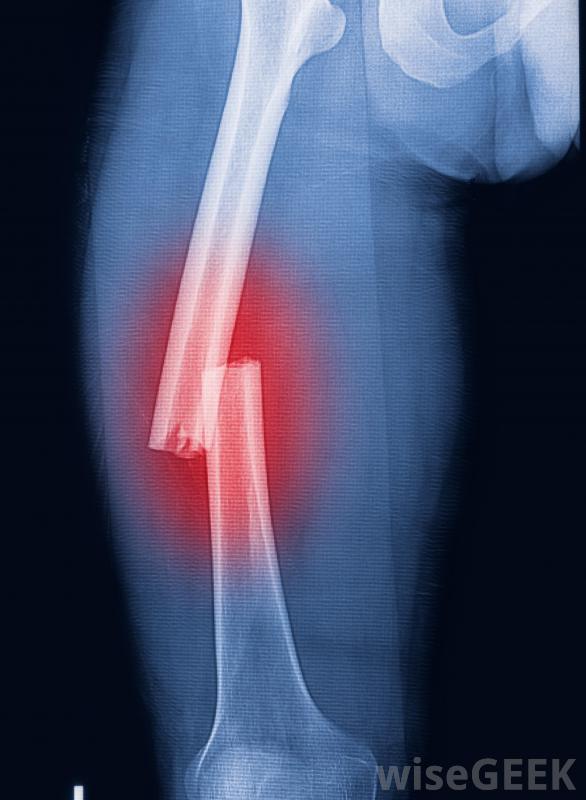

手部严重的肌肉痉挛可能会使使用牙刷变得困难。肌肉骨骼损伤,尤其是股骨或大腿骨骨折,几乎总是如此引起严重的肌肉疼痛和痉挛。这是由于肌肉有时剧烈收缩而引起的,这反过来又会导致骨骼切割和周围软组织"刺伤"的锯齿状末端的运动。夹板的使用不仅可以大大减少失血量,还可以止止止疼